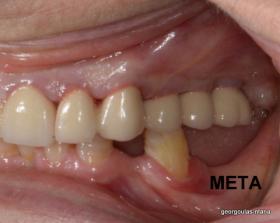

ΑΝΟΙΚΤΗ ΑΝΥΨΩΣΗ ΙΓΜΟΡΕΙΟΥ Κ ΤΟΠΟΘΕΤΗΣΗ 3 ΕΜΦΥΤΕΥΜΑΤΩΝ

Στην ασθενή αυτή πραγματοποιήθηκε ανοικτή ανύψωση ιγμορείου άνω αριστερά. Σε πρώτη φάση πραγματοποιήθηκε η οστική αύξηση και 6 μήνες μετά τοποθετήθηκαν 3 εμφυτεύματα. Τόσο στην πανοραμική όσο και στην τομογραφία κωνικής δέσμης (CBCT) που πραγματοποιήθηκαν 6 μήνες μετά την ανύψωση είναι εμφανής ο σχηματισμός οστού. Η τελευταία ακτινογραφία και φωτογραφία λήφθηκαν 5 χρόνια μετά την προσθετική αποκατάσταση.